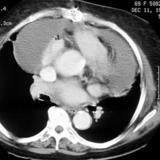

Part'l absc peric cu

Date: 07/23/2006

Views: 2423